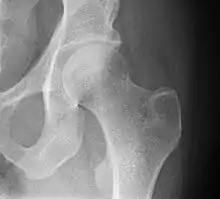

Radiograph of a healthy human hip joint

The hip joint is a ball and socket synovial joint formed by the articulation of the rounded head of the femur and the cup-like acetabulum of the pelvis.[5] The socket of the acetabulum is pointing downwards and anterolaterally. The socket is also turned such that the outer edge of its roof is more lateral than outer edge of the floor.[5] It forms the primary connection between the bones of the lower limb and the axial skeleton of the trunk and pelvis. Both joint surfaces are covered with a strong but lubricated layer called articular hyaline cartilage.

The cuplike acetabulum forms at the union of three pelvic bones — the ilium, pubis, and ischium.[6] The Y-shaped growth plate that separates them, the triradiate cartilage, is fused definitively at ages 14–16.[7] It is a special type of spheroidal or ball and socket joint where the roughly spherical femoral head is largely contained within the acetabulum and has an average radius of curvature of 2.5 cm.[8] The acetabulum grasps almost half the femoral ball, a grip deepened by a ring-shaped fibrocartilaginous lip, the acetabular labrum, which extends the joint beyond the equator.[6] The centre of the acetabulum (fovea) does not articulate to anything. Instead, it is lined with fat pad and attached to ligamentum teres. The acetabular labrum is horse-shoe shaped. Its inferior notch is bridged by transverse acetabular ligament.[5] The joint space between the femoral head and the superior acetabulum is normally between 2 and 7 mm.[9]